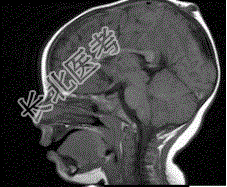

- 单项选择题男孩,1岁。有头皮损伤史, CT检查,最可能的诊断是

A、脑膨出

B、胼胝体发育不全

C、Dandy-Walker综合征

D、狭颅症

E、脑积水